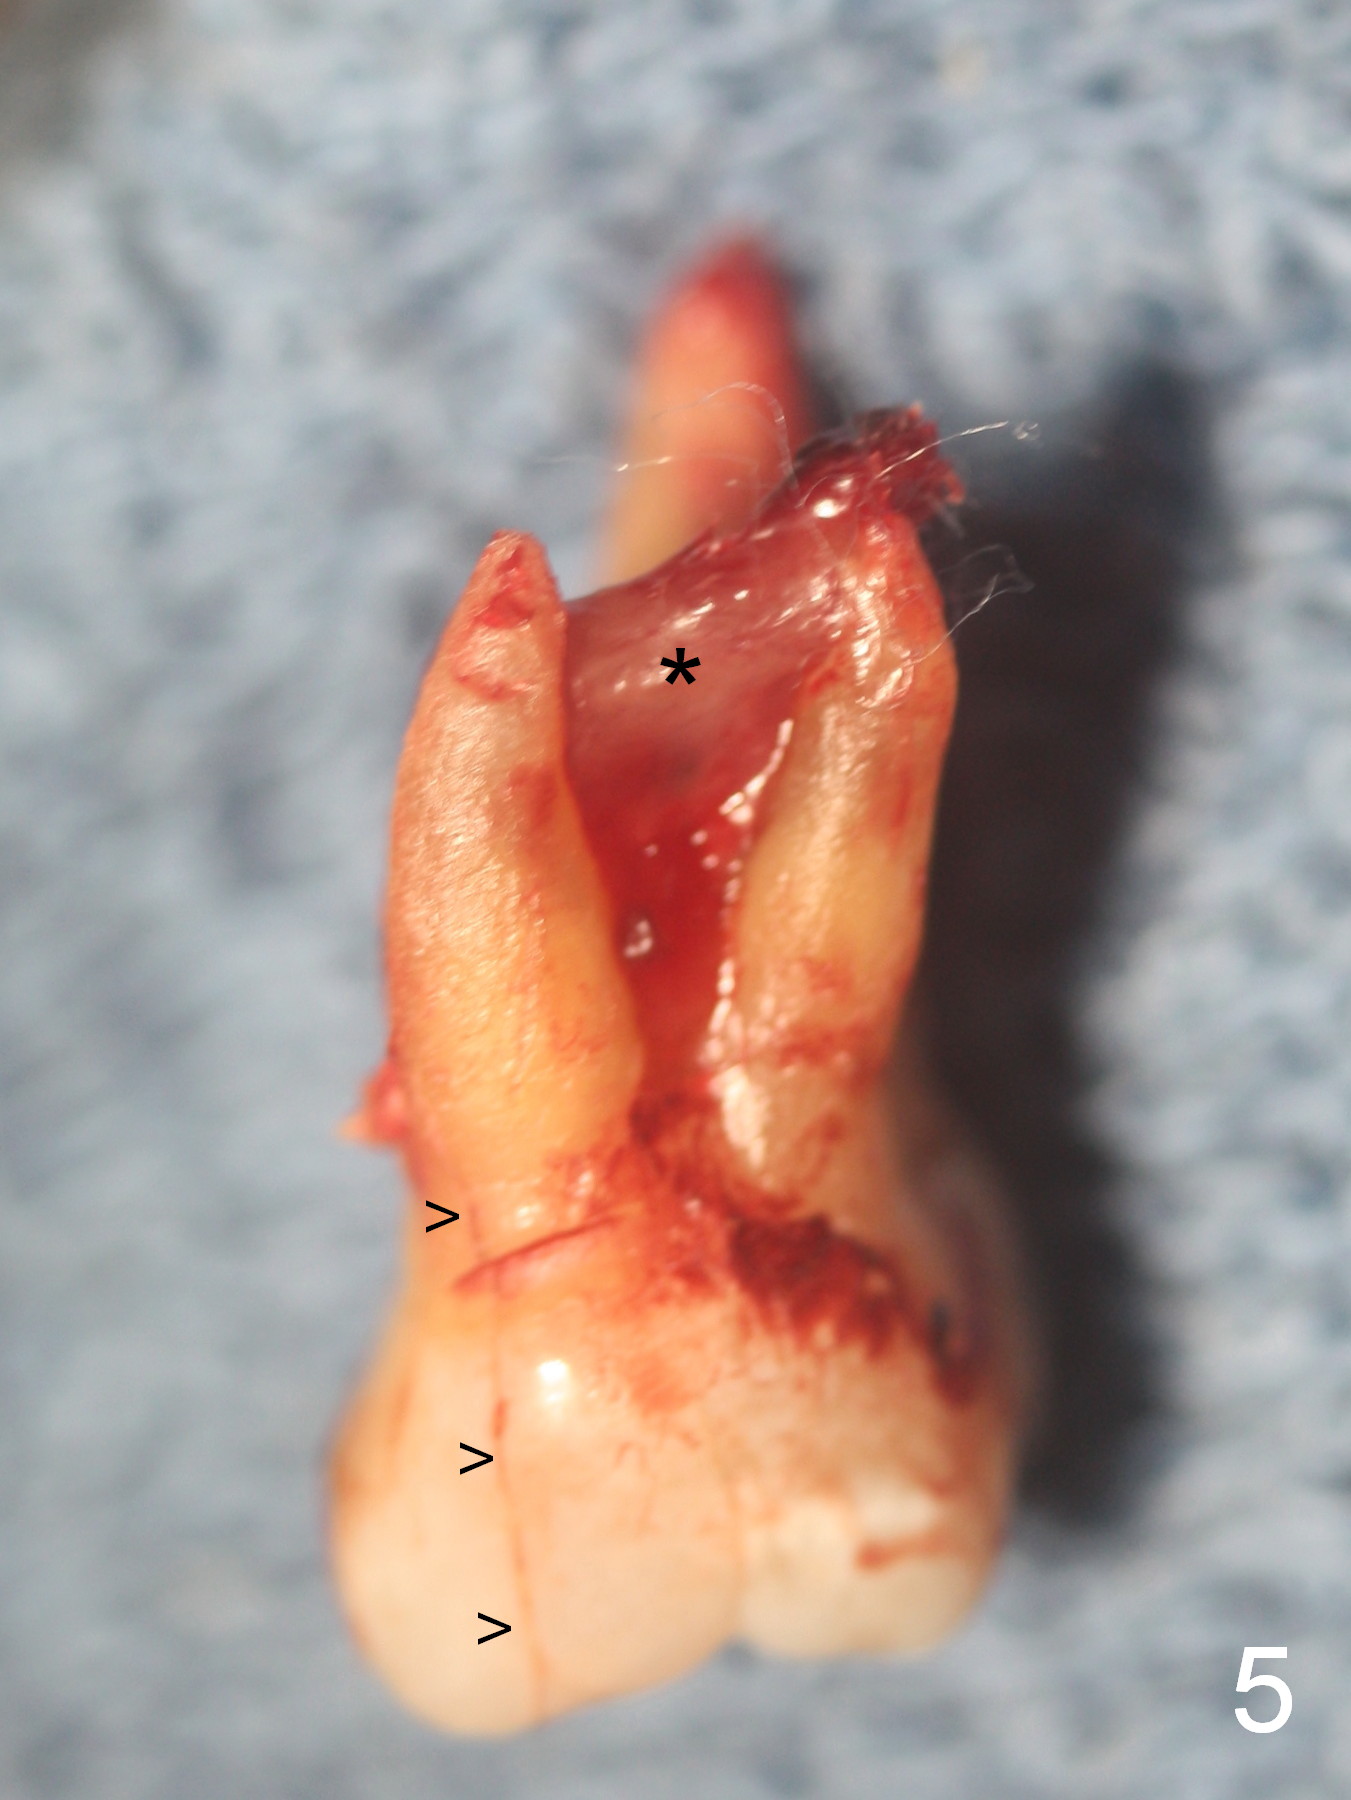

When the tooth is extracted, the lingual crack line (Fig.4 white <) is contiguous with the mesiobuccal one (black >). The latter corresponds to the white arrowheads in Fig.2. In all the crack line is extensive. The buccal and palatal plates are defective coronally. The large granulation tissue in the furca (Fig.5 *) suggests bone loss in the crestal septum. Most surprising is a crack line in the distal surface of the tooth #13 (Fig.6 ^) and in the mesial surface of #15 (Fig.7). Night guard will be fabricated after an implant crown is cemented at #14.